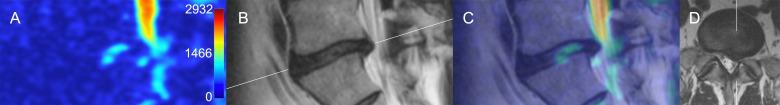

T1-weighted, T2-weighted and diffusion weighted (DWI) MR images of 100 consecutive patients admitted to the spinal surgery service were assessed. ADC maps were generated from DWI images using Osyrix software. The ADC values and characteristic ADC maps were assessed in the regions of interest over the different pathological entities of the lumbar spine.

The study included 452 lumbar vertebral segments available for analysis of ADCs. Characteristic ADC map features were identified for protrusion, extrusion and sequester types of lumbar disk herniations, spondylolisthesis, reactive Modic endplate changes, Pfirrmann grades of IVD degeneration, and compromised spinal nerves. Compromised nerve roots had significantly higher mean ADC values than adjacent (p < 0.001), contralateral (p < 0.001) or adjacent contralateral (p < 0.001) nerve roots. Compared to the normal bone marrow, Modic I changes showed higher ADC values (p = 0.01) and Modic 2 changes showed lower ADC values (p = 0.02) respectively. ADC values correlated with the Pfirrmann grading, however differed from herniated and non-herniated disks of the matched Pfirrmann 3 and 4 grades.

Quantitative and qualitative evaluation of ADC mapping may provide additional useful information regarding the fluid dynamics of the degenerated spine and may complement standard MRI imaging protocol for the comprehensive assessment of surgical patients with lumbar spine pathology. ADC maps were advantageous in differentiating reactive bone marrow changes, and more precise assessment of the disk degeneration state. ADC mapping of compressed nerve roots showed promise but requires further investigation on a larger cohort of patients.